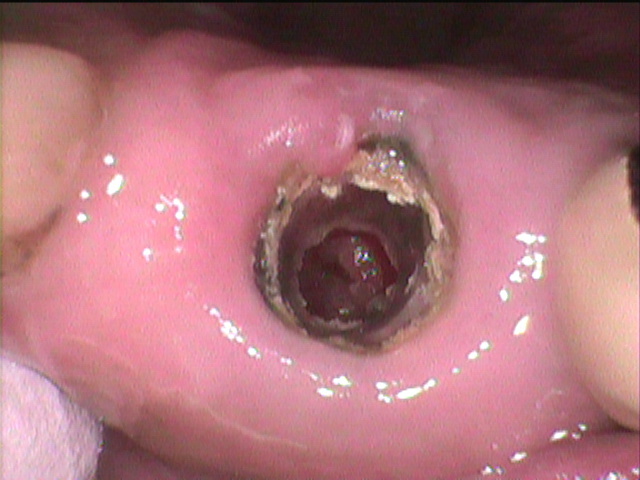

根尖切除の履歴のある歯が脱離して来院

歯ぎしりもひどく何度も脱離しています。

歯ぎしりでメタルボンドクラウンに

穴が空いています。

消炎処置後

すでに歯は限界に達しています。

根管の先端部分は底抜けの状態で

歯周組織が見えている状況です。

通常なら抜歯の適応ですが、これを残すための努力をしました。